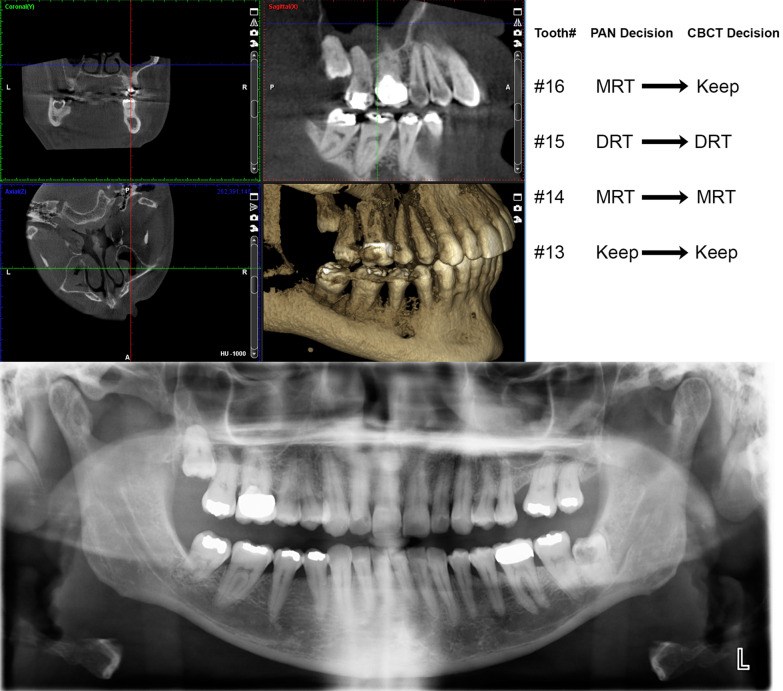

Background: The study compared clinical decisions regarding root angulation correction and root proximity based on the interpretation of Panoramic (PAN) versus Cone-Beam Computed Tomography (CBCT) images.

Methods: A total of 864 teeth from 36 existing, radiographic patient records at a university dental clinic with concurrent PAN and CBCT images were assessed using PANs, then using CBCTs in a blinded manner by two orthodontists. Teeth were rated regarding the need for root repositioning, the direction of repositioning and existence of root proximity. Frequencies, rating time and intra- and inter-examiner Cohen's Kappa were calculated.

Results: There was 73.7-84.5% agreement between PAN-based and CBCT-based orthodontists' decisions regarding the need to reposition roots. Root proximity was more frequently reported on PANs than CBCTs by one examiner (p = 0.001 and p = 0.168). Both PANs and CBCTs had moderate to substantial intra-examiner, within-radiograph-type reliability with Kappa values of 0.686-0.79 for PANs, and 0.661 for CBCTs (p < 0.001). Inter-examiner and inter-radiograph-type Kappa values ranged from 0.414 to 0.51 (p < 0.001). Using CBCT decisions as a reference, 78.9% of PAN decisions were coincident, 9.3% would have been repositioned on CBCT but not on PAN, 11.3% would not have been repositioned on CBCT but were on PAN, and 0.3% would have been repositioned in the opposite direction on CBCT versus PAN. Additionally, CBCT images required more time per tooth to assess than PANs (p < 0.001).

Conclusions: PAN-based clinical decisions regarding root angulation had comparable statistical reliability and substantial agreement with CBCT-based clinical decisions.